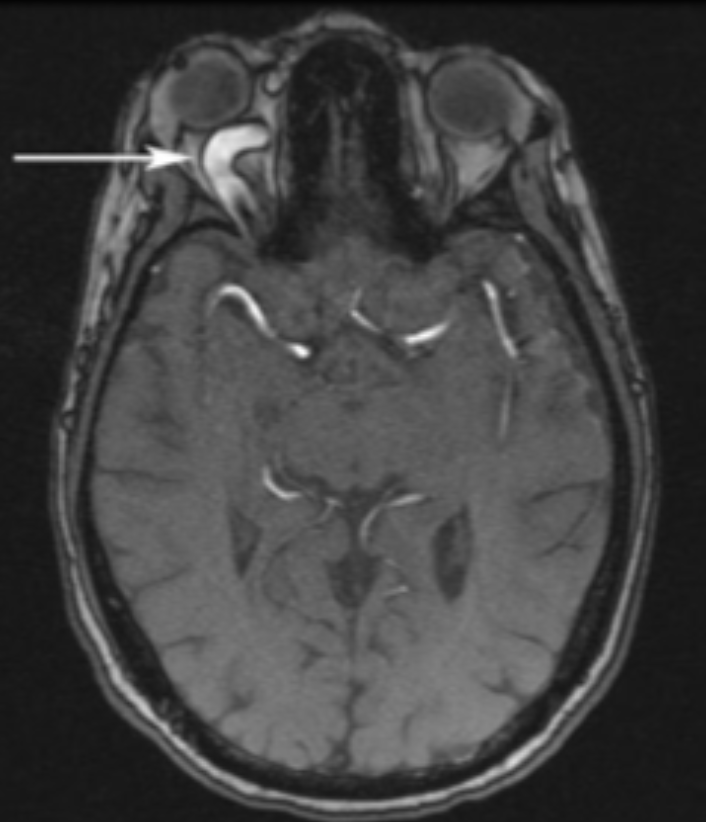

Qual a alteração clássica nos exames de imagem na fístula carótido-cavernosa?

Aumento do calibre da veia oftálmica superior

Embolização por radiologia intervencionista